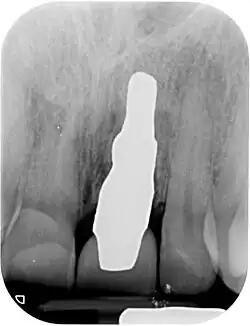

An ensuing clinical study in humans in 2002 with root-identical titanium implants showed excellent primary stability, but, disappointingly, nearly half the implants failed after 9 months. This particular implant system was not recommended for clinical use, and clinical trials were stopped.[28][29]

A new attempt was made by Pirker et al 2004 in a human trial with root analogue zirconia implants, but this time by applying differentiated osseoingration on the surface. In 2011 he reported 90% success rate with this method in a 2.5 year human trial.[16]

Mangano et al in Italy in 2012 reported the successful clinical use of a custom-made root analogue implant made by direct laser metal forming (DLMF) from a CBCT scan. This demonstrated that it is possible to combine CBCT 3D data and CAD/CAM technology to manufacture root-analogue implants with sufficient precision.[30]

In 2012 Moin et al in The Netherlands investigated the accuracy of CBCT and CAD/CAM technology on individual root analogue implants, and concluded that this technique could potentially provide accurate dental implants for immediate placement.[31]